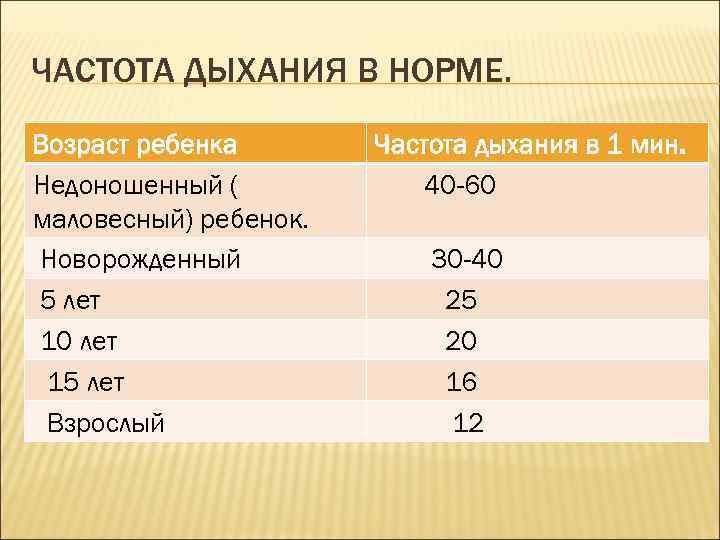

ЧАСТОТА ДЫХАНИЯ В НОРМЕ. Возраст ребенка Недоношенный ( маловесный) ребенок. Новорожденный 5 лет 10 лет 15 лет Взрослый Частота дыхания в 1 мин. 40 -60 30 -40 25 20 16 12